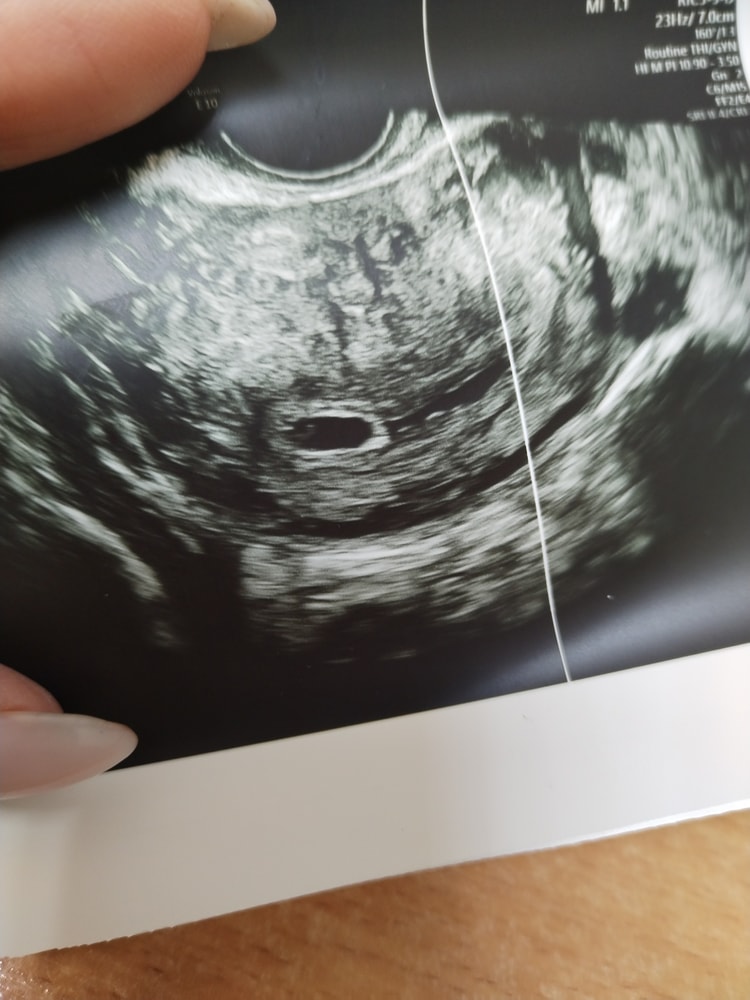

УЗИ 6 недель

Марина, просто на экране, когда мерили размер, длина была 0.87мм, ширину не помню. Я сначала подумала, что это и есть размер ПЯ 8,7мм. Или они как-то по-другому и ещё с учётом ширины считают🤔 Спросила сколько ПЯ, сказали 6,9...

Марина, Изображение

Наталья, по фото размер не оценить,они обычно или два размера пишут или три,а считают свд,т.е к примеру пя 8*5*6 свд будет 8+5+6=19 и это разделить на 3 и получается свд 6,3,если два размера то сложить и разделить на 2 и тоже будет свд пя

Марина, Изображение Это с прошлого УЗИ, тут тогда размер 4,4 получается, а мне сказали 5. Видимо округлили

Наталья, да 4,4 свд здесь округлили до 5

Катерина, плодное яйцо отстаёт по размеру на 6 дней

Вики, по месячным вчера ровно 6 недель было, по плодному яйцу вчера поставили 5,1, плодное яйцо было 6,9мм. Меня смущает плохой рост ПЯ, в четверг было 4,4мм, а оно должно рости 1мм в день